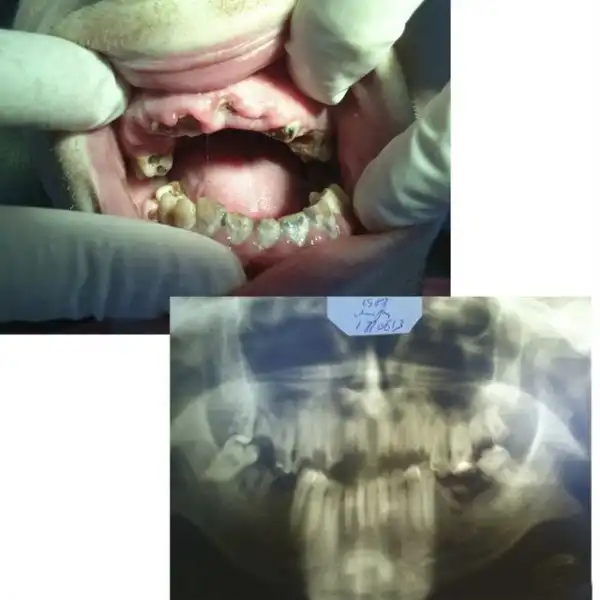

Вот один интересный товарищ. Не мой пациент, но просили посмотреть… Несколько месяцев назад получил травму, перелом челюсти, но врачам об этом не говорил, догадались сами, лечился в областной больнице, был выписан, все было хорошо вроде бы уже, но недавно обратился к нам с остеомиелитом, флегмоной щечной области, неконсолидировавшимся( несросшимся) переломом нижней челюсти слева. Чтоб дойти до такого состояния нужно терпеть с появления первых симптомов с месяц минимум… На фотке виден не корень зуба. Это секвестр — некротизированный, отторгающийся участок кости нижней челюсти. Мужик поедет к челюстно- лицевым хирургам…

Это секвестр, который я достал пинцетом, просто он уже практически свободно лежал в полости рта и не был связан с нижней челюстью, остальные секвестры будут удалять челюстно-лицевые хирурги в стационаре. Операция называется секвестрэктомия. В поликлинике такие операции делать нельзя.